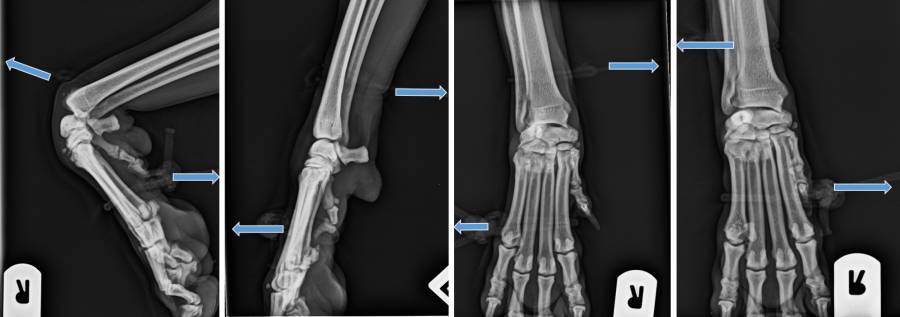

Röntgen Ellbogen

Röntgen Unterarm

Röntgen Karpus und Pfoten